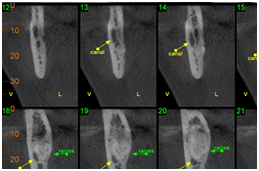

• Visualizar tamanho, forma e número de canais radiculares

Endodontia (obliteração radicular no 11)